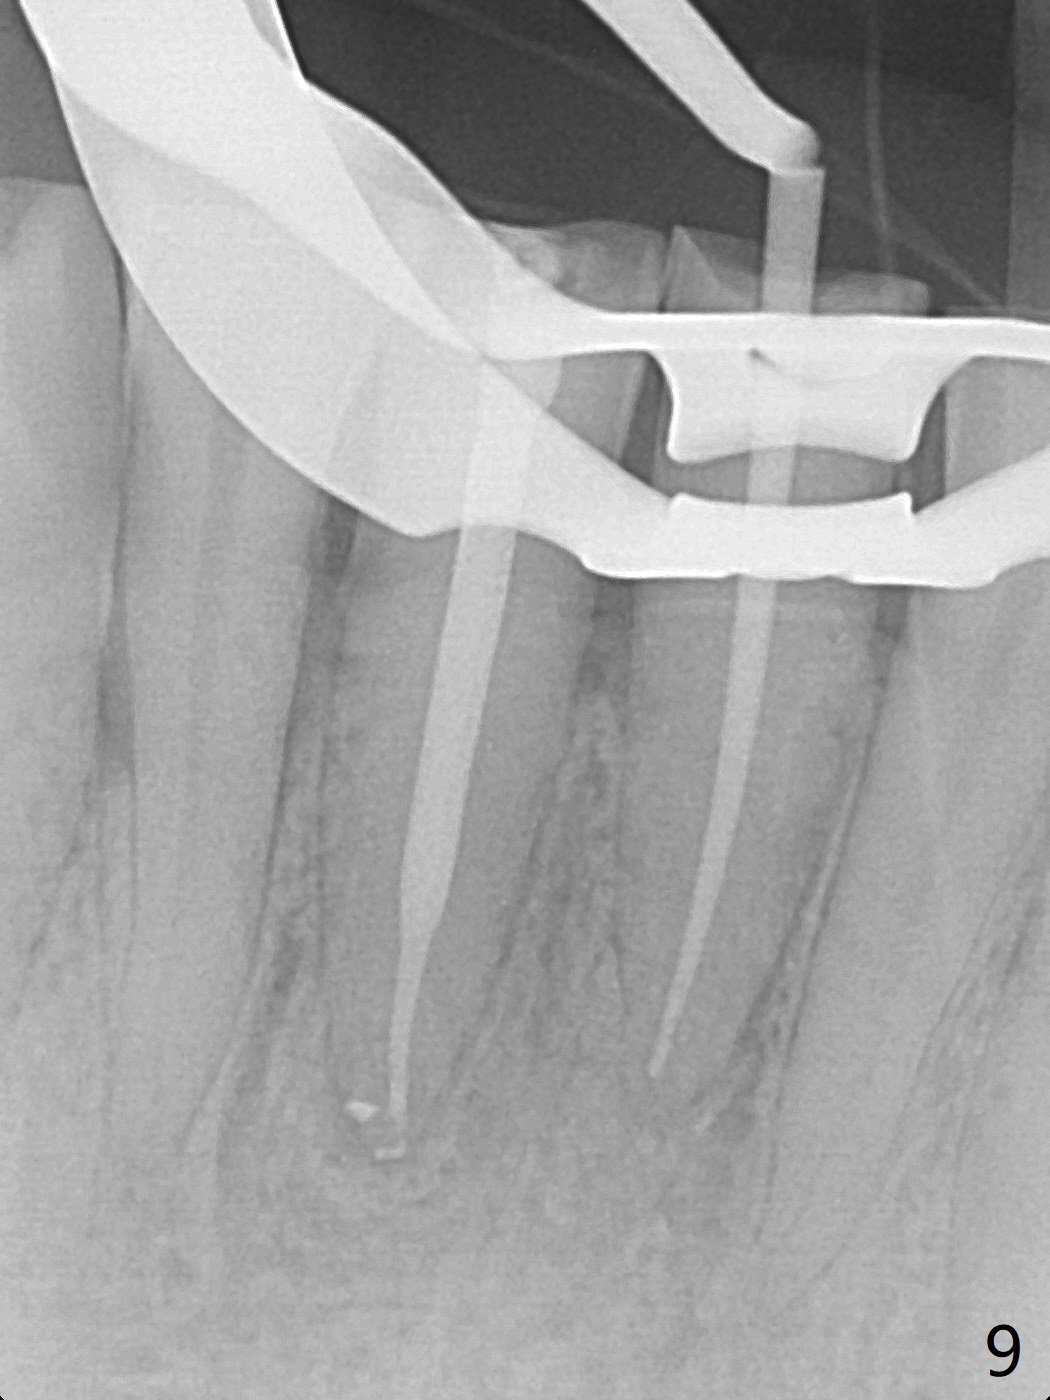

A 45-year-old man has had a chronic fistula associated with the tooth #25 (Fig.1). There is purulent discharge sometimes. After debridement with hand files #10-20 and rotary one 30/06, a master cone 30/.06 is inserted incompletely (Fig.2). After rotary files 30/.08 at 16.0 mm and 30/.10 at 15.0 mm and hand files 10-20 at 17 mm, the master cone is apparently inserted to the WL. With application of Endo Sequence Sealer (syringe), the master cone is reinserted (Fig.3). When the rubber dam is removed, the sealer is found to have expelled from the fistula. With an endo curette (Fig.5), the sealer is removed from the deepest portion of the sinus tract (apex of the tooth). What do you want to know the outcome of the supplementary surgical maneuver? The sealer is gone (Fig.6). The immediately supplementary treatment avoids a separate apicoectomy. No fistula is noted <2 weeks postop (Fig.7). The attrition is due to #8 and 9 veneers, fabricated 8 years earlier. The tooth #24 is symptomatic with loss of incisal composite nearly 4 years postop (Fig.8 <). After 30/.04 gutta percha (GP) try in (Fig.9), RCT is finished without accessory GP (Fig.10).